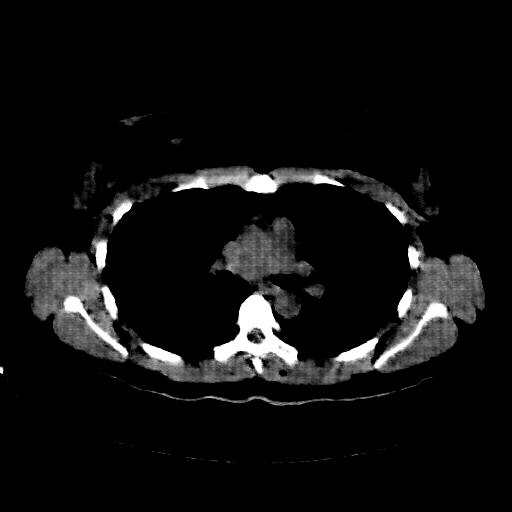

Image Grid

4Γ—3 grid: Rows show different image types (Original NATIVE, Reconstructed NATIVE, Original VENOUS, Generated VENOUS), Columns show windowing techniques (No Window, Lung Window, Mediastinum Window)

Lung window (WL -600, WW 1500 β†’ Low βˆ’1350, High +150)